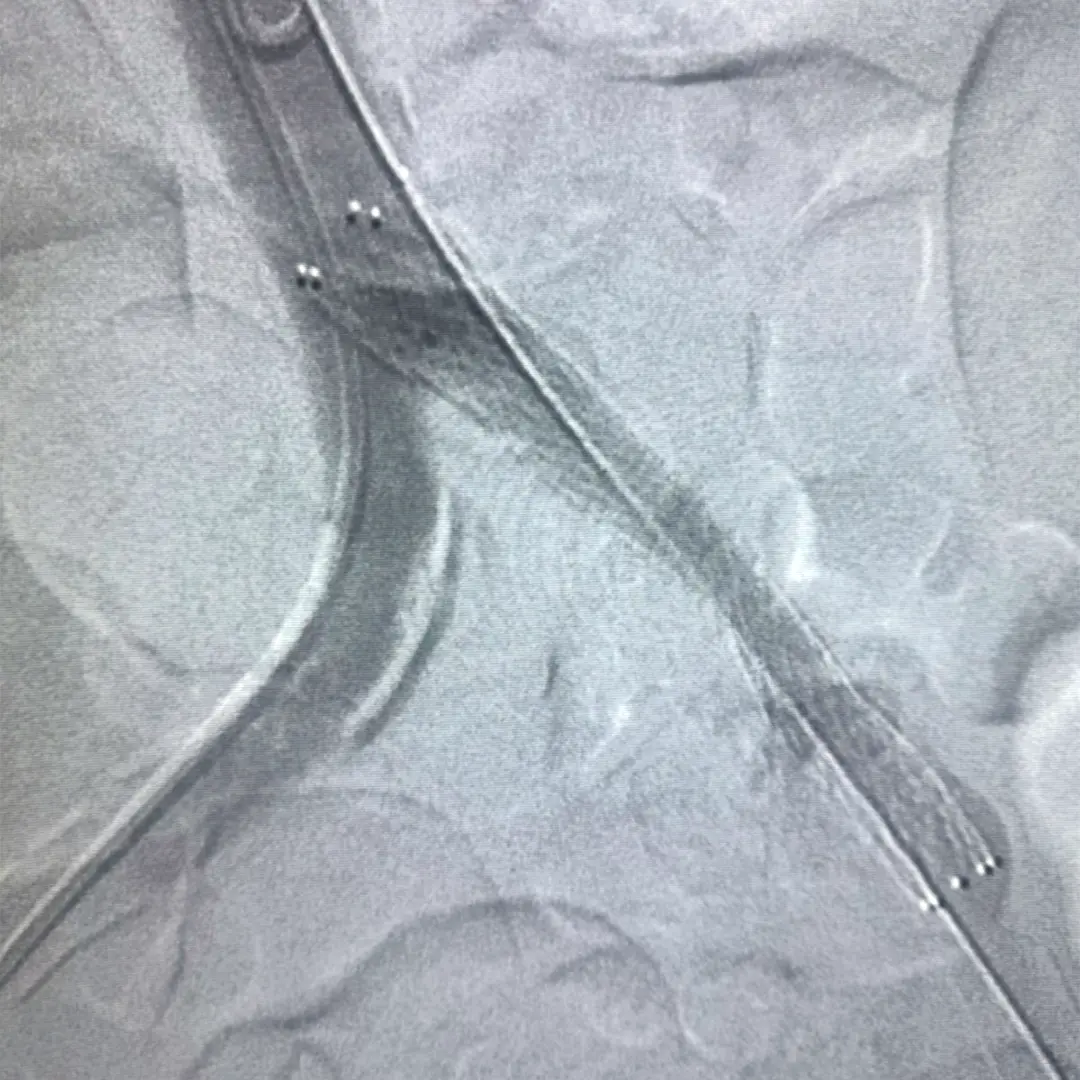

Angioplastía Stent (remodelación de arteria)

Tratamiento que se realiza para abrir los vasos sanguíneos estrechos o bloqueados, en el cual se introduce una guía microscópica desinflada y una vez introducida se infla para abrir el paso en la arteria.

Se coloca una prótesis llamada stent (un pequeño tubo de malla de metal que se expande dentro de una arteria del corazón) para recuperar el flujo sanguíneo.